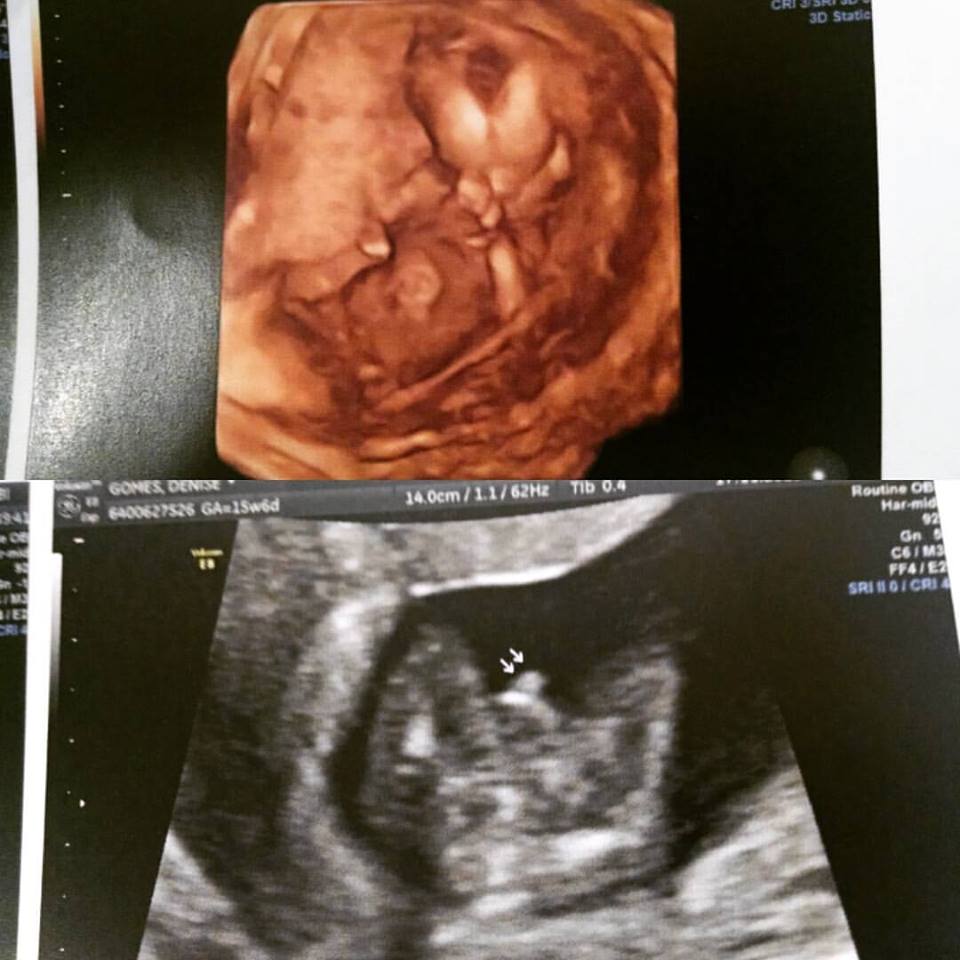

- Quando posso saber o sexo do bebê? Hoje em dias temos duas maneiras de saber o sexo do bebê. A mais precoce é através de um exame de sangue que pode ser realizado a partir da oitava semana de gestação, chamado de Sexagem Fetal, ou através do exame de ultrassom que normalmente confirma o sexo após a 16ª semana gestacional.